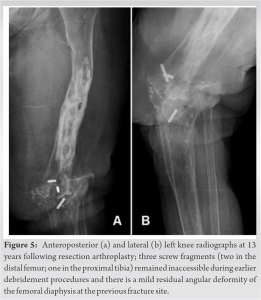

She remained clinically stable and was able to transfer independently to and from wheelchair. At 13-year follow-up (Fig. 5), there was no radiological evidence of osteomyelitis progression and, particularly in view of her age and accumulating comorbidities (such as atrial fibrillation), the patient was satisfied with her decision, long-term antibiotic therapy, and functional status.

The patient was treated at our institution with removal of metalwork (although three screw fragments around the knee were irretrievable) and radical debridement using the Lautenbach method [6]. Suction irrigation with teicoplanin was used for 3 weeks following the operation, and she also received 5 weeks of intravenous followed by oral flucloxacillin, according to the sensitivities of multiple intraoperative cultures, which had grown coagulase-negative Staphylococci and coryneforms. Knee arthrodesis was re-attempted 5 weeks after the first stage procedure (Fig. 4) with the application of a Sheffield external ring fixator (Orthofix Medical Inc., Lewisville, TX, USA) [7,8], and an extended post-operative course of oral co-amoxiclav, as per microbiology. Shortly after being discharged home, she fell and sustained a displaced periprosthetic fracture of her left mid-femoral shaft, which was reduced and managed with revision and reinforcement of the proximal ring of the external fixator. Although the fracture united with only a mild residual angular deformity within 4 months, there was no progress toward successful fusion of the knee. Unfortunately, serial radiographs revealed bony destruction, and white blood cell scintigraphy showed diffuse uptake in the distal femur, strongly indicative of osteomyelitis. However, the patient was clinically stable and bloods were normal, except for a moderately elevated CRP (35 mg/L) and ESR (60 mm/h). The patient consequently underwent removal of the external fixator and further extensive debridement; the screw fragments within the distal femur and proximal tibia remained inaccessible. Multiple intraoperative samples grew methicillin-resistant Staphylococcus aureus, which was treated with an extended course of intravenous vancomycin and teicoplanin. Due to poor bone quality and previous recurrent infection, which had necessitated multiple operations, she was deemed unsuitable for reimplantation and we therefore discussed the options of above-knee amputation (AKA) or remaining with a permanent resection arthroplasty. The patient reported that she did not have any pain and wanted to retain her limb, despite this meaning that she would require ongoing antibiotic suppression with oral doxycycline. Regular follow-up indicated that inflammatory markers were quiescent.